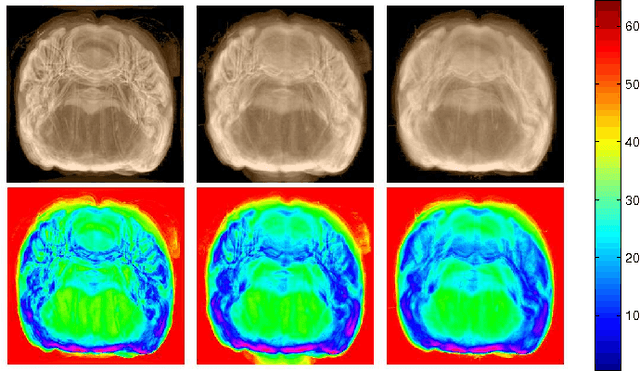

Abstract:Arterial spin labeling (ASL) perfusion MRI provides a non-invasive way to quantify cerebral blood flow (CBF) but it still suffers from a low signal-to-noise-ratio (SNR). Using deep machine learning (DL), several groups have shown encouraging denoising results. Interestingly, the improvement was obtained when the deep neural network was trained using noise-contaminated surrogate reference because of the lack of golden standard high quality ASL CBF images. More strikingly, the output of these DL ASL networks (ASLDN) showed even higher SNR than the surrogate reference. This phenomenon indicates a learning-from-noise capability of deep networks for ASL CBF image denoising, which can be further enhanced by network optimization. In this study, we proposed a new ASLDN to test whether similar or even better ASL CBF image quality can be achieved in the case of highly noisy training reference. Different experiments were performed to validate the learning-from-noise hypothesis. The results showed that the learning-from-noise strategy produced better output quality than ASLDN trained with relatively high SNR reference.

Abstract:Arterial spin labeling perfusion MRI is a noninvasive technique for measuring quantitative cerebral blood flow (CBF), but the measurement is subject to a low signal-to-noise-ratio(SNR). Various post-processing methods have been proposed to denoise ASL MRI but only provide moderate improvement. Deep learning (DL) is an emerging technique that can learn the most representative signal from data without prior modeling which can be highly complex and analytically indescribable. The purpose of this study was to assess whether the record breaking performance of DL can be translated into ASL MRI denoising. We used convolutional neural network (CNN) to build the DL ASL denosing model (DL-ASL) to inherently consider the inter-voxel correlations. To better guide DL-ASL training, we incorporated prior knowledge about ASL MRI: the structural similarity between ASL CBF map and grey matter probability map. A relatively large sample data were used to train the model which was subsequently applied to a new set of data for testing. Experimental results showed that DL-ASL achieved state-of-the-art denoising performance for ASL MRI as compared to current routine methods in terms of higher SNR, keeping CBF quantification quality while shorten the acquisition time by 75%, and automatic partial volume correction.